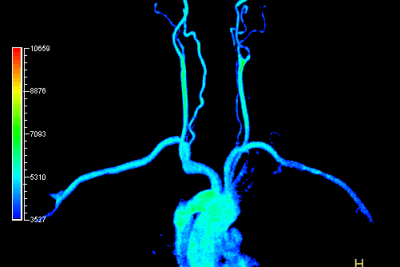

Beyin hastalıklarının tanı, tedavi ve takibinde gelişmiş görüntüleme teknolojilerinin kullanımı büyük önem taşımaktadır. Bu teknolojinin etkin kullanımı, hekimlere ayırıcı tanı koyma ve tedavi sürecindeki gelişmeleri takip etme imkanı sağlayarak hastalara büyük fayda sağlamaktadır. Kurum, beyin hastalıklarında en ileri görüntüleme cihazlarını kullanmakta olup, Türkiye'de ileri beyin MR tekniklerini ilk uygulayan kurumlar arasındadır.